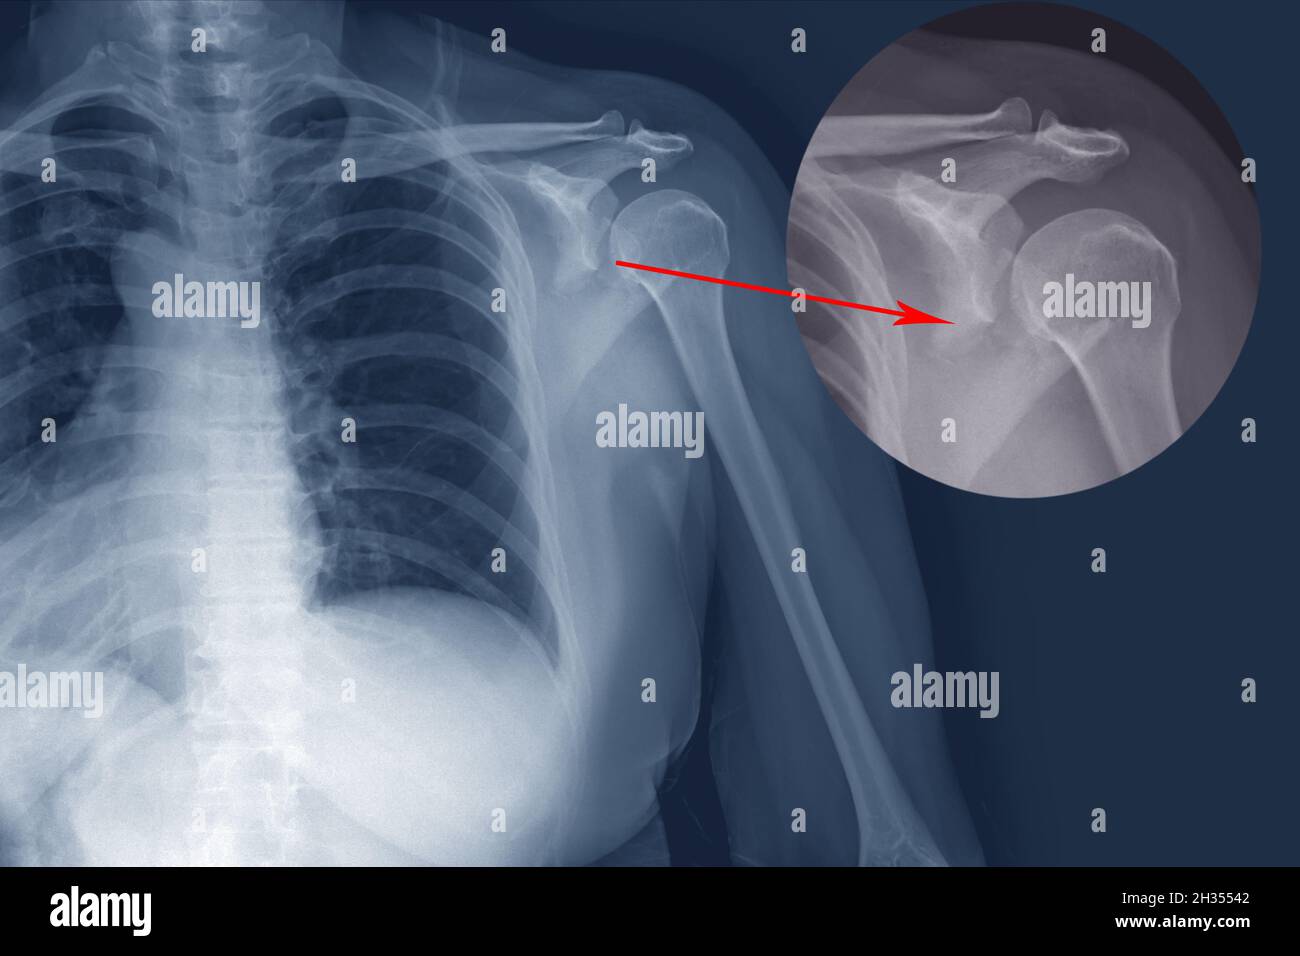

Xray of shoulder with fractured scapula Stock Photo 52414851 Alamy Scapula Fracture X Ray    an appropriate set of radiographs in the setting of acute scapular trauma includes ap, grashey, axillary, and. This article will review the use of diagnostic imaging for evaluating traumatic scapular fracture and describe imaging findings associated with operative management indications. Check the scapula carefully in the context of trauma.   scapula fractures are uncommon fractures to the shoulder girdle. Scapula Fracture X Ray.